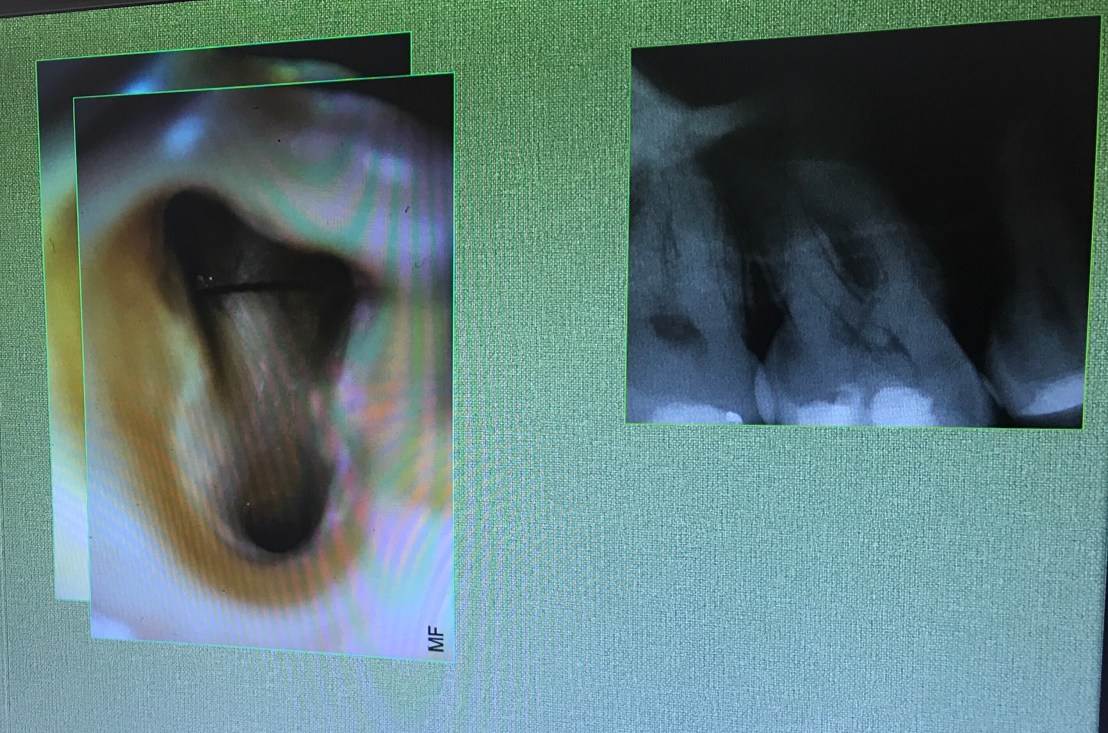

Lecture ต่อมา คือหลักการซ่อมแซม perforate

Definition

การ Dx เช่น Apex locator ร้องก่อนถึง WL , ลักษณะเหงือกบริเวณใกล้ปลายรากจะปกติ แต่บริเวณ crestal bone จะแย่ลง เป็นต้น

อันนี้คือ case จริงครับ ส่วนที่ Outline ไว้ตรงกลางคือ รอย Perforate

repair ใช้ MTA และ wet cotton (เพื่อให้ set)

อีก case

จุดสีเหลือง คือ canal ที่ถูกต้อง

วงกลมสีแดง แสดงส่วนที่ถูก repair ด้วย MTA

การ repair โดยใช้ Internal matrix

Internal matrix คือการใช้วัสดุปิดชั้นแรกสุดเข้าไปก่อน เพือป้องกันวัสดุอีกตัวที่ใช้ repair ไม่ให้รั่วไหลออกมา

วัสดุที่ใช้เป็น matrix ชั้นแรก Collaplug

เนื่องจากขนาดของมันใหญ่กว่ารอยทะลุครับ ต้องมีการตัดออกให้พอดี

หน้าที่คือ stop bleed เป็น matrix ล้อมรอบ MTA หรือ Biodentine ไว้ ไม่ให้ออกนอก canal

และวัสดุที่ใส่ลงไปเป็นชั้นที่ 2